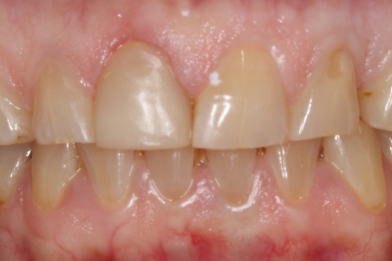

Реставрация верхних резцов с закрытием диастемы

Евсеенкова Дарья Эдуардовна -